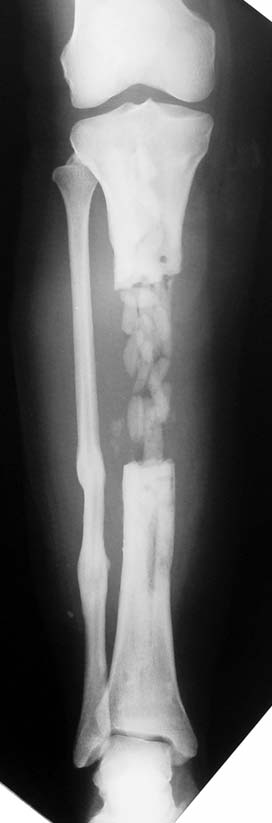

Chronic osteomyelitis leads to necrosis of bone and soft tissues. Dead bone is a nidus which hosts pathogenous microorganisms. Defence mechanisms of the host is usually not in optimum condition to deal with microorganisms. Antibiotics can’t reach the infection site because blood flow is disrupted. For these reasons, dead bone has to be completely removed by radical debridement.

Appropriate radical debridement necessitates excision of all necrotic bone and soft tissues, and frequently causes instability at the involved extremity. The remaining bone and soft tissue defect has to be fixed and reconstructed. The distraction osteogenesis method of Ilizarov is used successfully for achievement of union, correction of the deformity, elimination of limb length inequality and reconstruction of segmental bone defects.